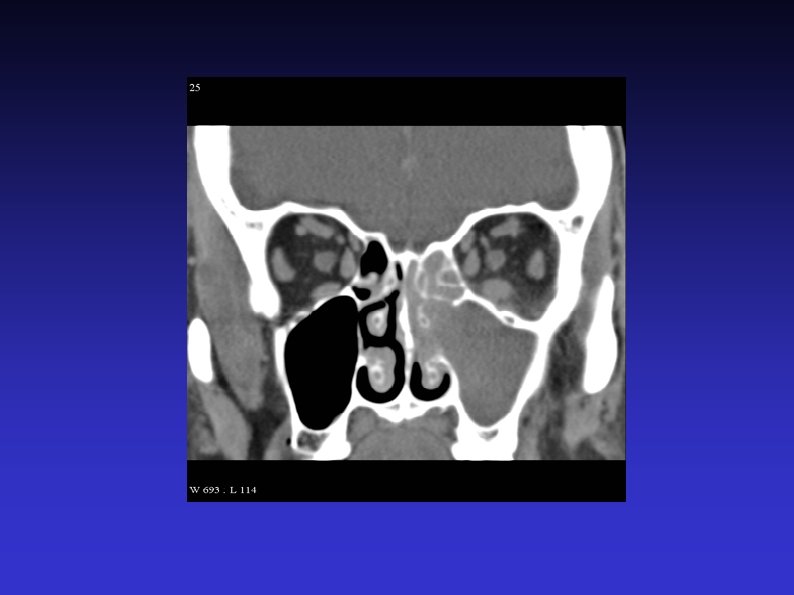

Examination of the nose 5) Anterior rhinoscopy Thudichum’s speculum vs otoscope Obvious lesions Mucosa Septum Turbinates (and osteomeatal complex)